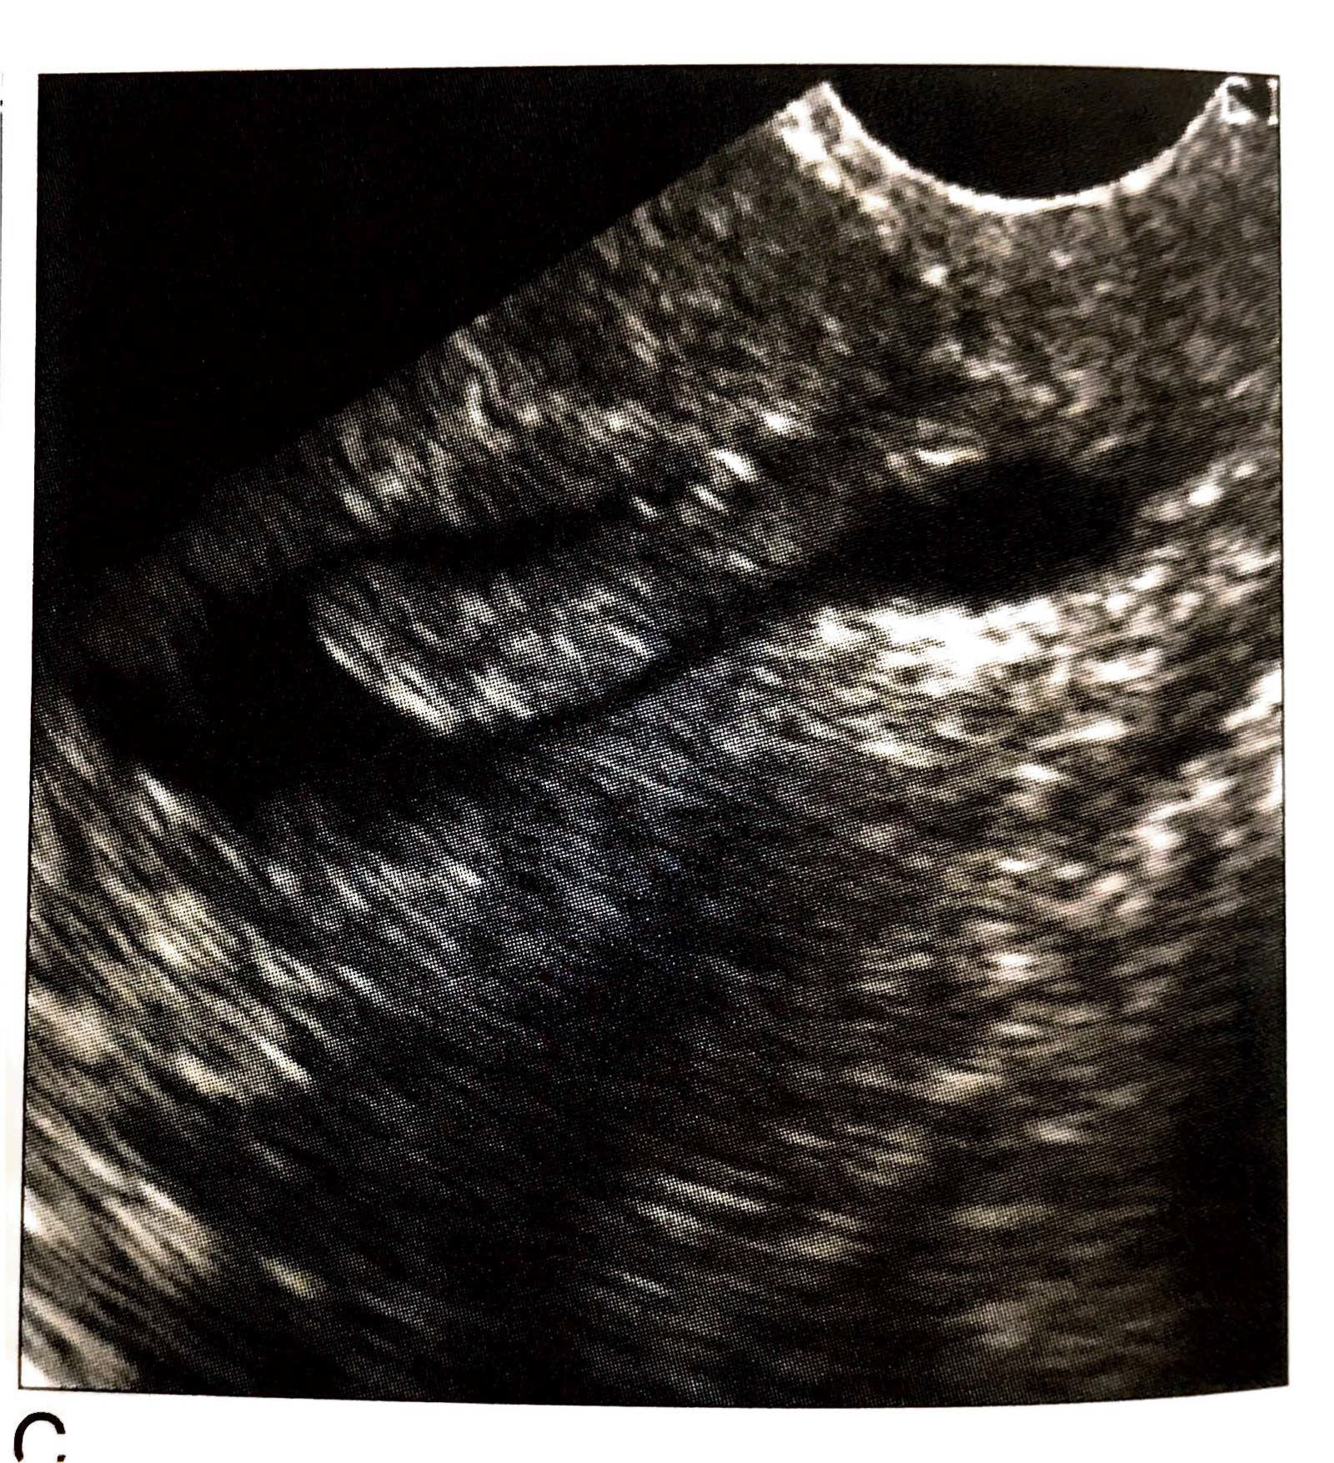

Uterine Synechia

interstitial/ cornual